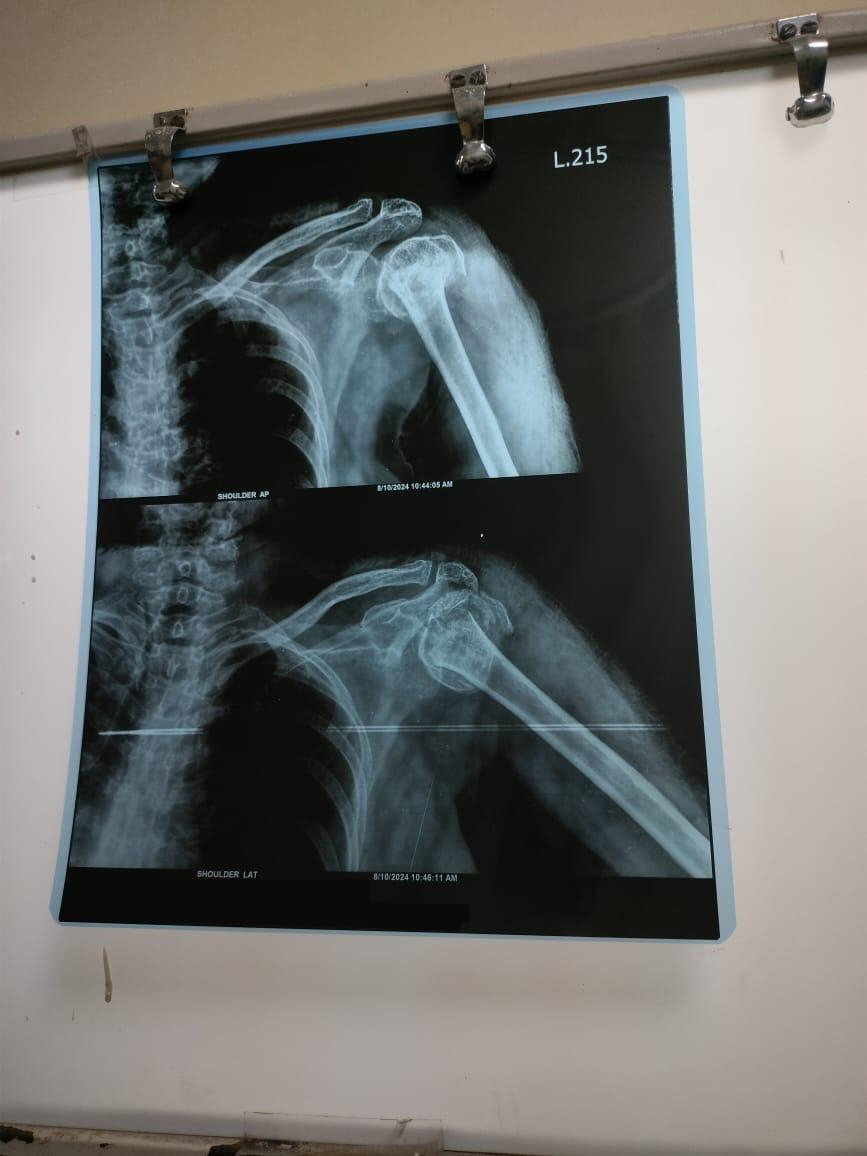

X-ray left shoulder external rotation ap view of SMT Indumati in 414A

Shoulder Surgery